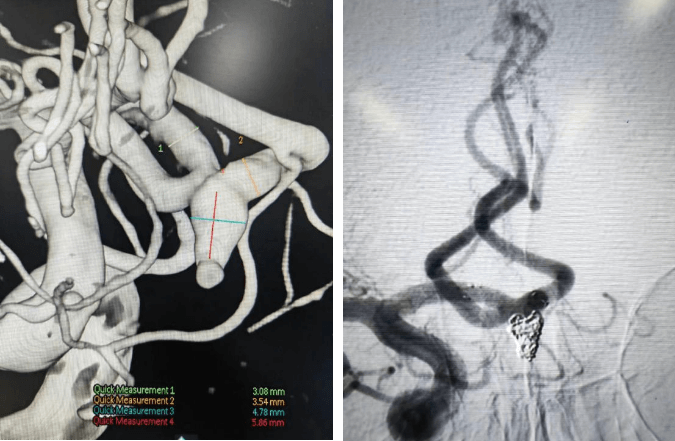

開顱夾閉動脈瘤手術(shù)

支架輔助動脈瘤栓塞術(shù)前、術(shù)后對比

術(shù)前血管畸形及介入治療后血管畸形消失(治愈出院)